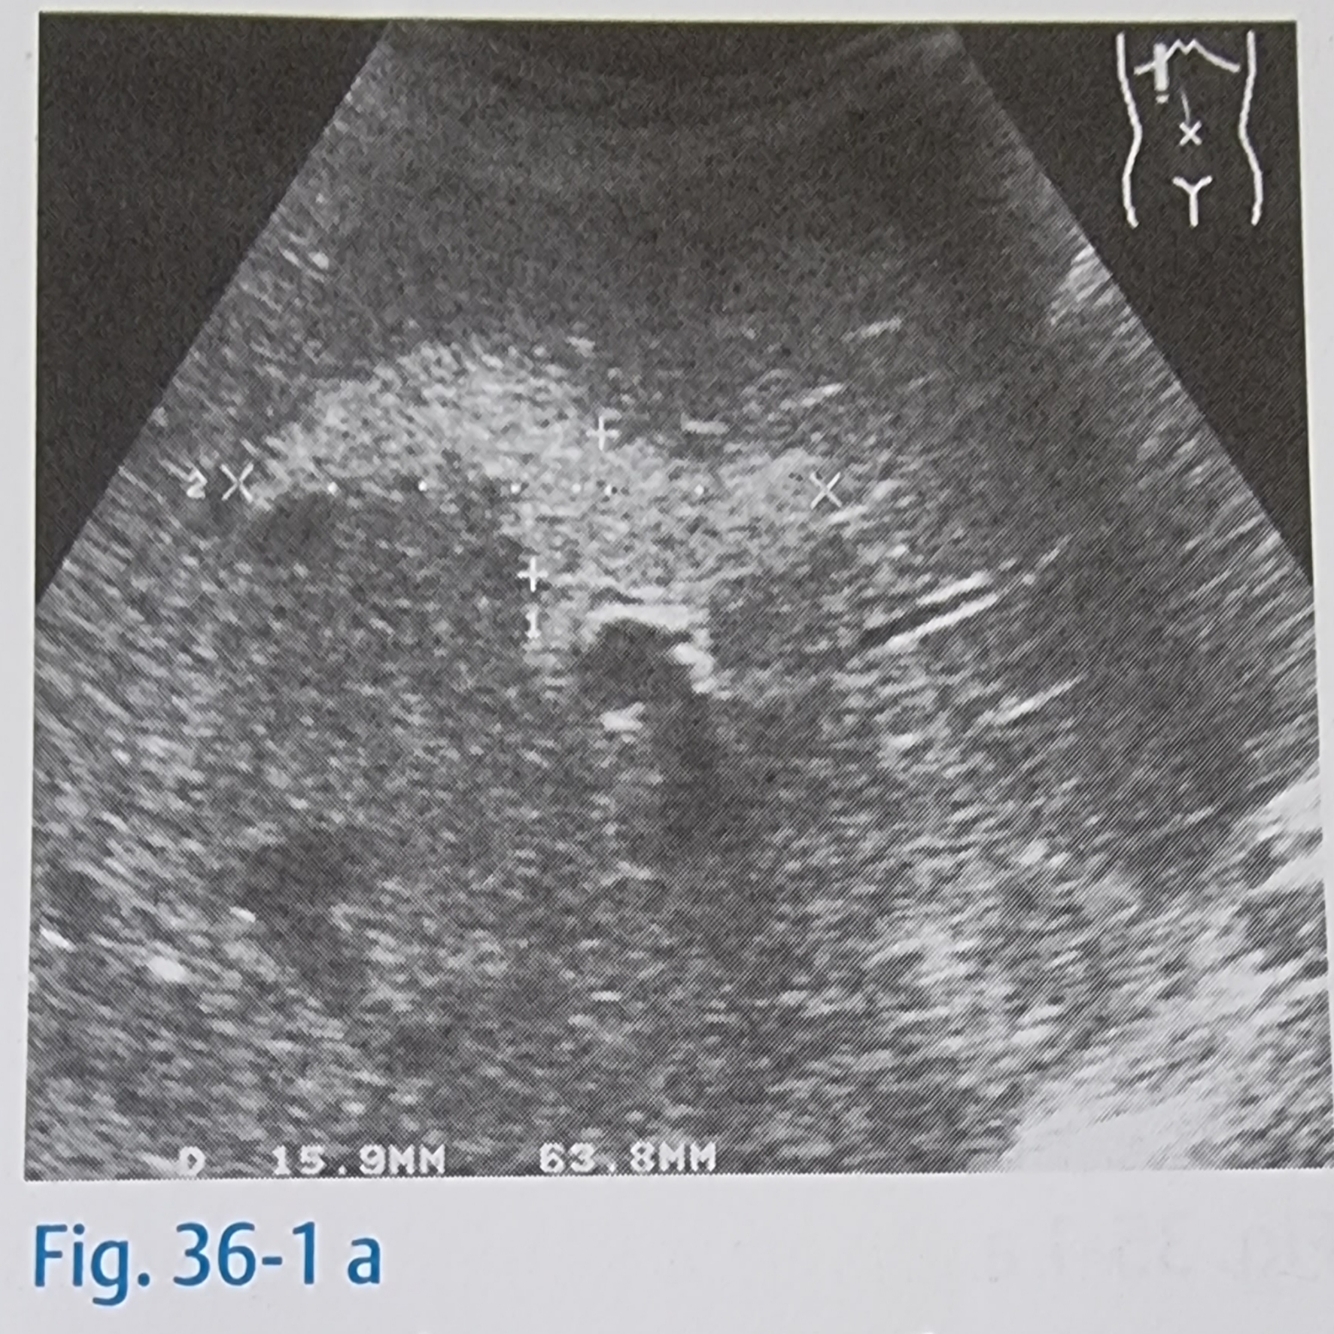

16

Q

O que seria a Hiperplasia Nodular Focal?

A

É um tumor benigno do fígado, mais frequente em mulheres que tomam anticoncepcionais orais